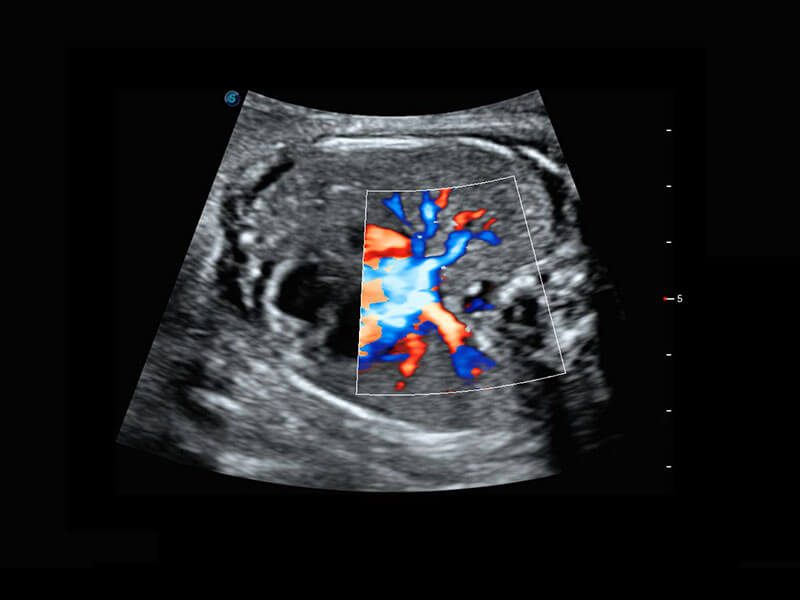

胎心筛查

P60搭载一系列胎儿心脏成像技术,实现精细的胎儿心脏评估。

• 四腔心血流